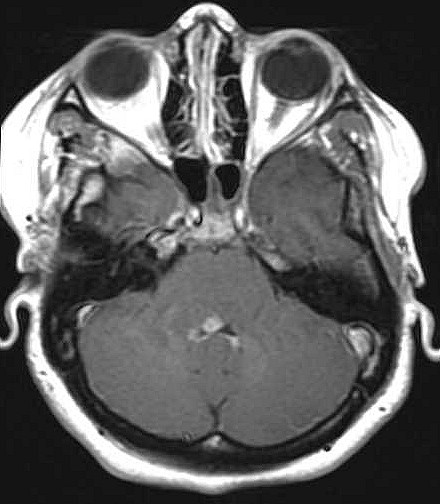

| Fem. 17a. |

| Nódulo sólido homogêneo preenchendo o III ventrículo, com limites precisos, com hipossinal em T1 e hipersinal em T2 e FLAIR, que se impregna por contraste paramagnético. Lesão menor implantada no assoalho do IV ventrículo provavelmente representa disseminação por via liquórica. |

| AXIAIS, FLAIR | T2 | |

| F. 17a. Tumor teratóide rabdóide atípico de III ventrículo. RM | HE | VIM, GFAP | HHF35, desmina, 1A4 | AE1AE3, EMA |